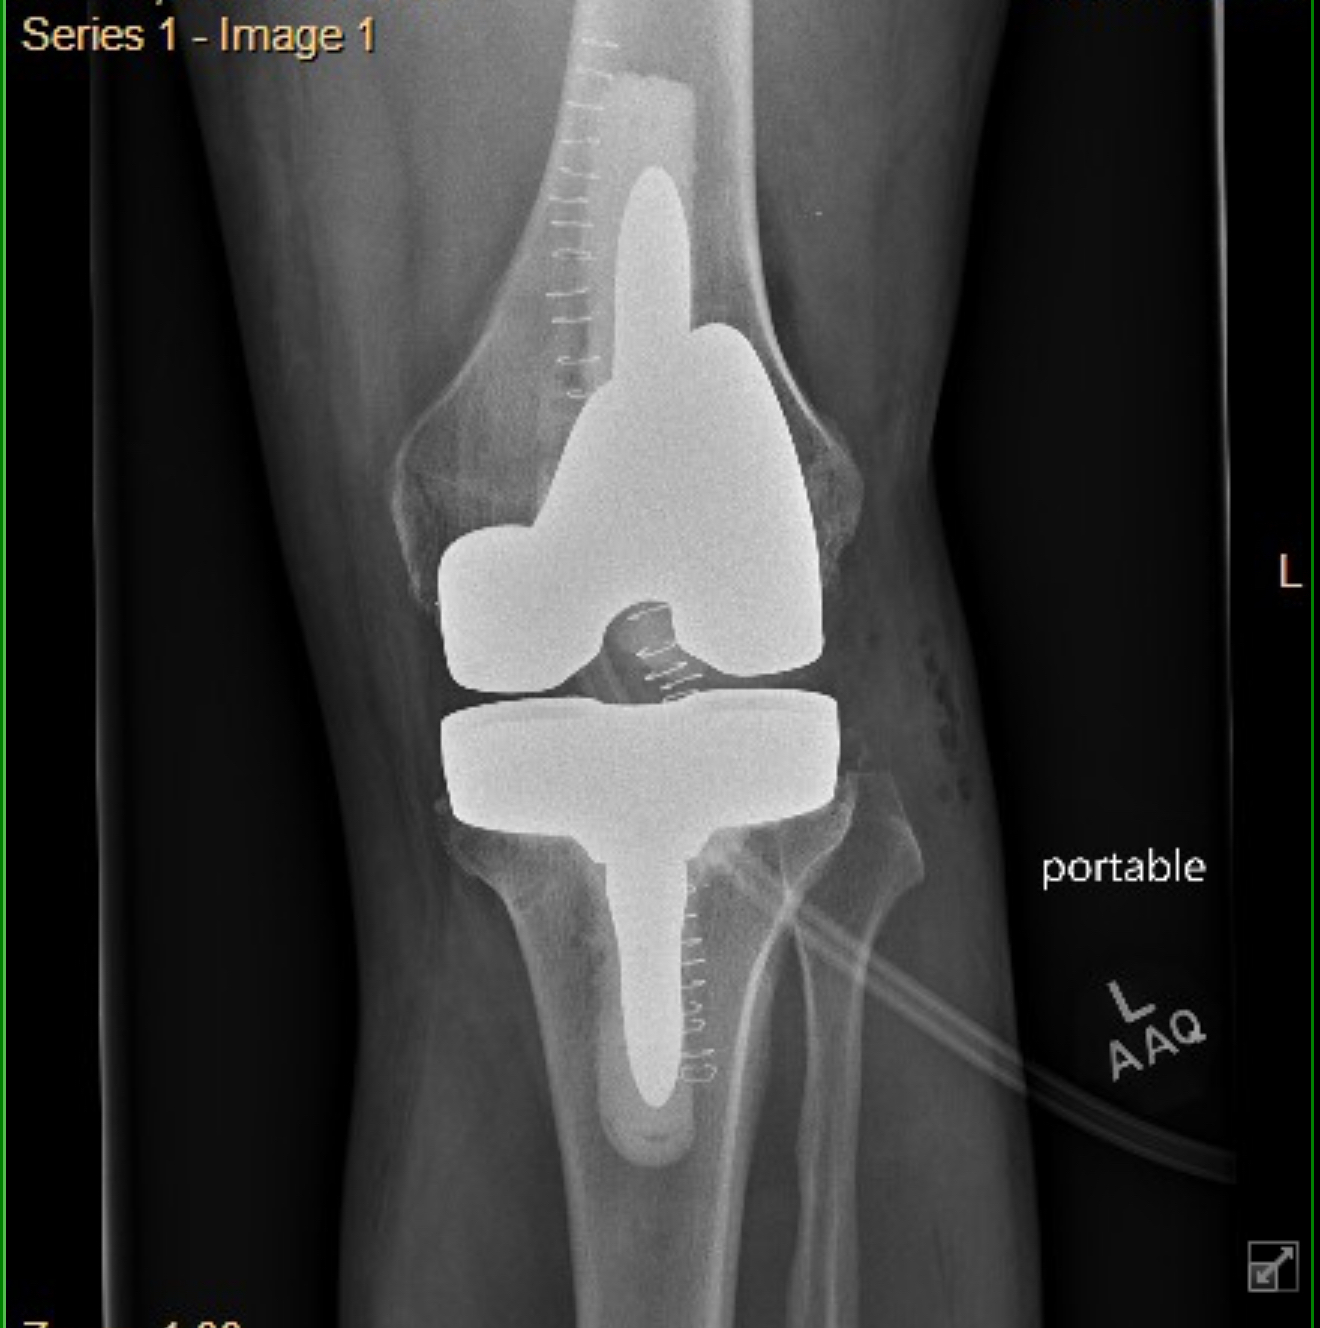

Left TKA Revision

Had the original TKA in Dec2020, never really got any relief. 4 1/2 years of living with and finally decided to see what can be done. Met with an ortho at Yale how specializes in revisions. Originally her plan was to just replace the plastic bearing surface on top of the tibial component with a thicker piece to try and stabilize the joint.

At the 4 week pre-op we both independently came to the conclusion that maybe it would be better to replace everything and start fresh.

Bit of a difference in hardware in the before and after x-rays:

After: